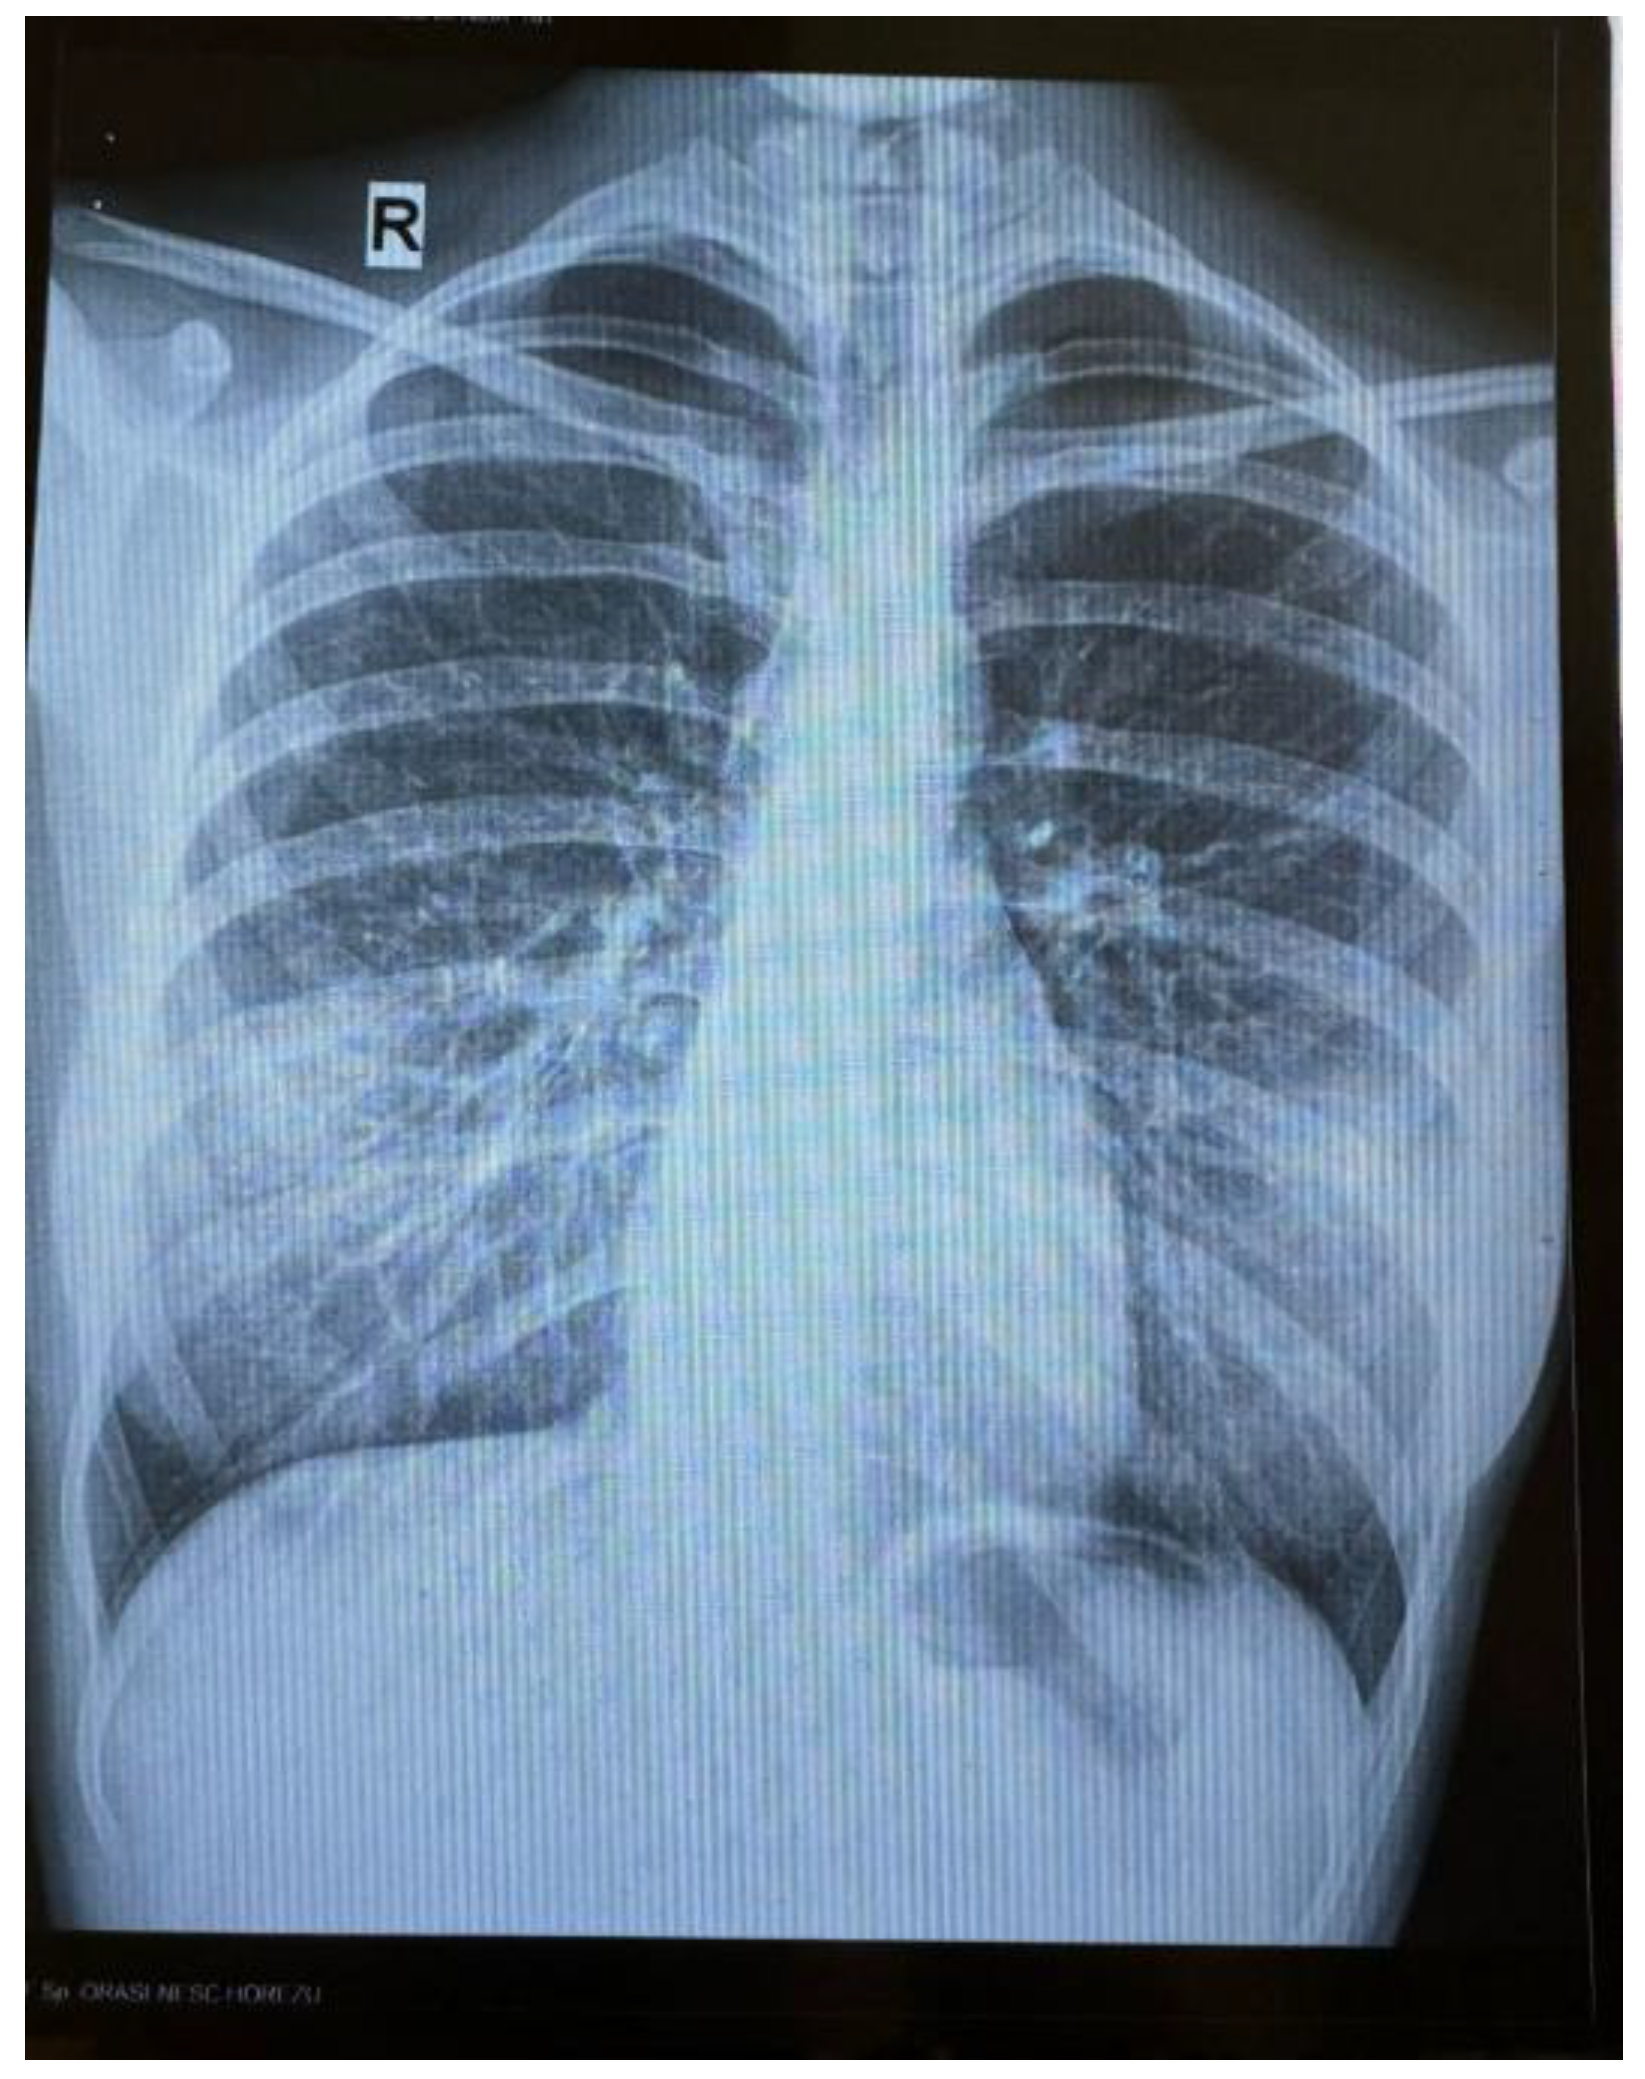

An 18-year-old female patient with no significant personal pathological history, is admitted in a hospital unit for symptoms consisting of continuous evening fever (maximum temperature of 40.3 °C), chills, night sweats, arthromyalgias, non-selective loss of appetite, involuntary decrease in weight (7 kg) and physical asthenia, with the onset approximately 8 months before (October 2023). During this period of time, the patient also manifested 3 respiratory complications: in November 2023—tonsillitis, for which she received macrolide treatment for 5 days; in January 2024—pneumonia, for which treatment was initiated with lincosamide for 7 days, which was later replaced, due to lack of clinical response, with tetracycline and second-generation cephalosporin for 5 days; in February 2024—influenza with influenza B virus, for which she received treatment with Oseltamivir. The patient underwent Gastroenterology and Internal Medicine consultations, after which symptomatic treatment was administered, without any improvement of the general condition. A radiographic aspect of bronchiectasis, completed with native chest CT, was identified in March (Figure 1), with no detection of an acute infectious process. In June 2024, the abdominal—pelvic ultrasound was normal, with no indication of hepatomegaly, splenomegaly or regional adenopathies. The patient also reported one to two episodes per week of nausea and vomiting since one and a half year ago, which she associated with the mental stress of returning to Romania, after only having lived in Spain. Last trip abroad was to Valencia, in October 2023. The patient denied any use of intravenous drugs or risky sexual behaviour.

Figure 1. Bronchiectasis aspect of the bilateral pulmonary hilae.